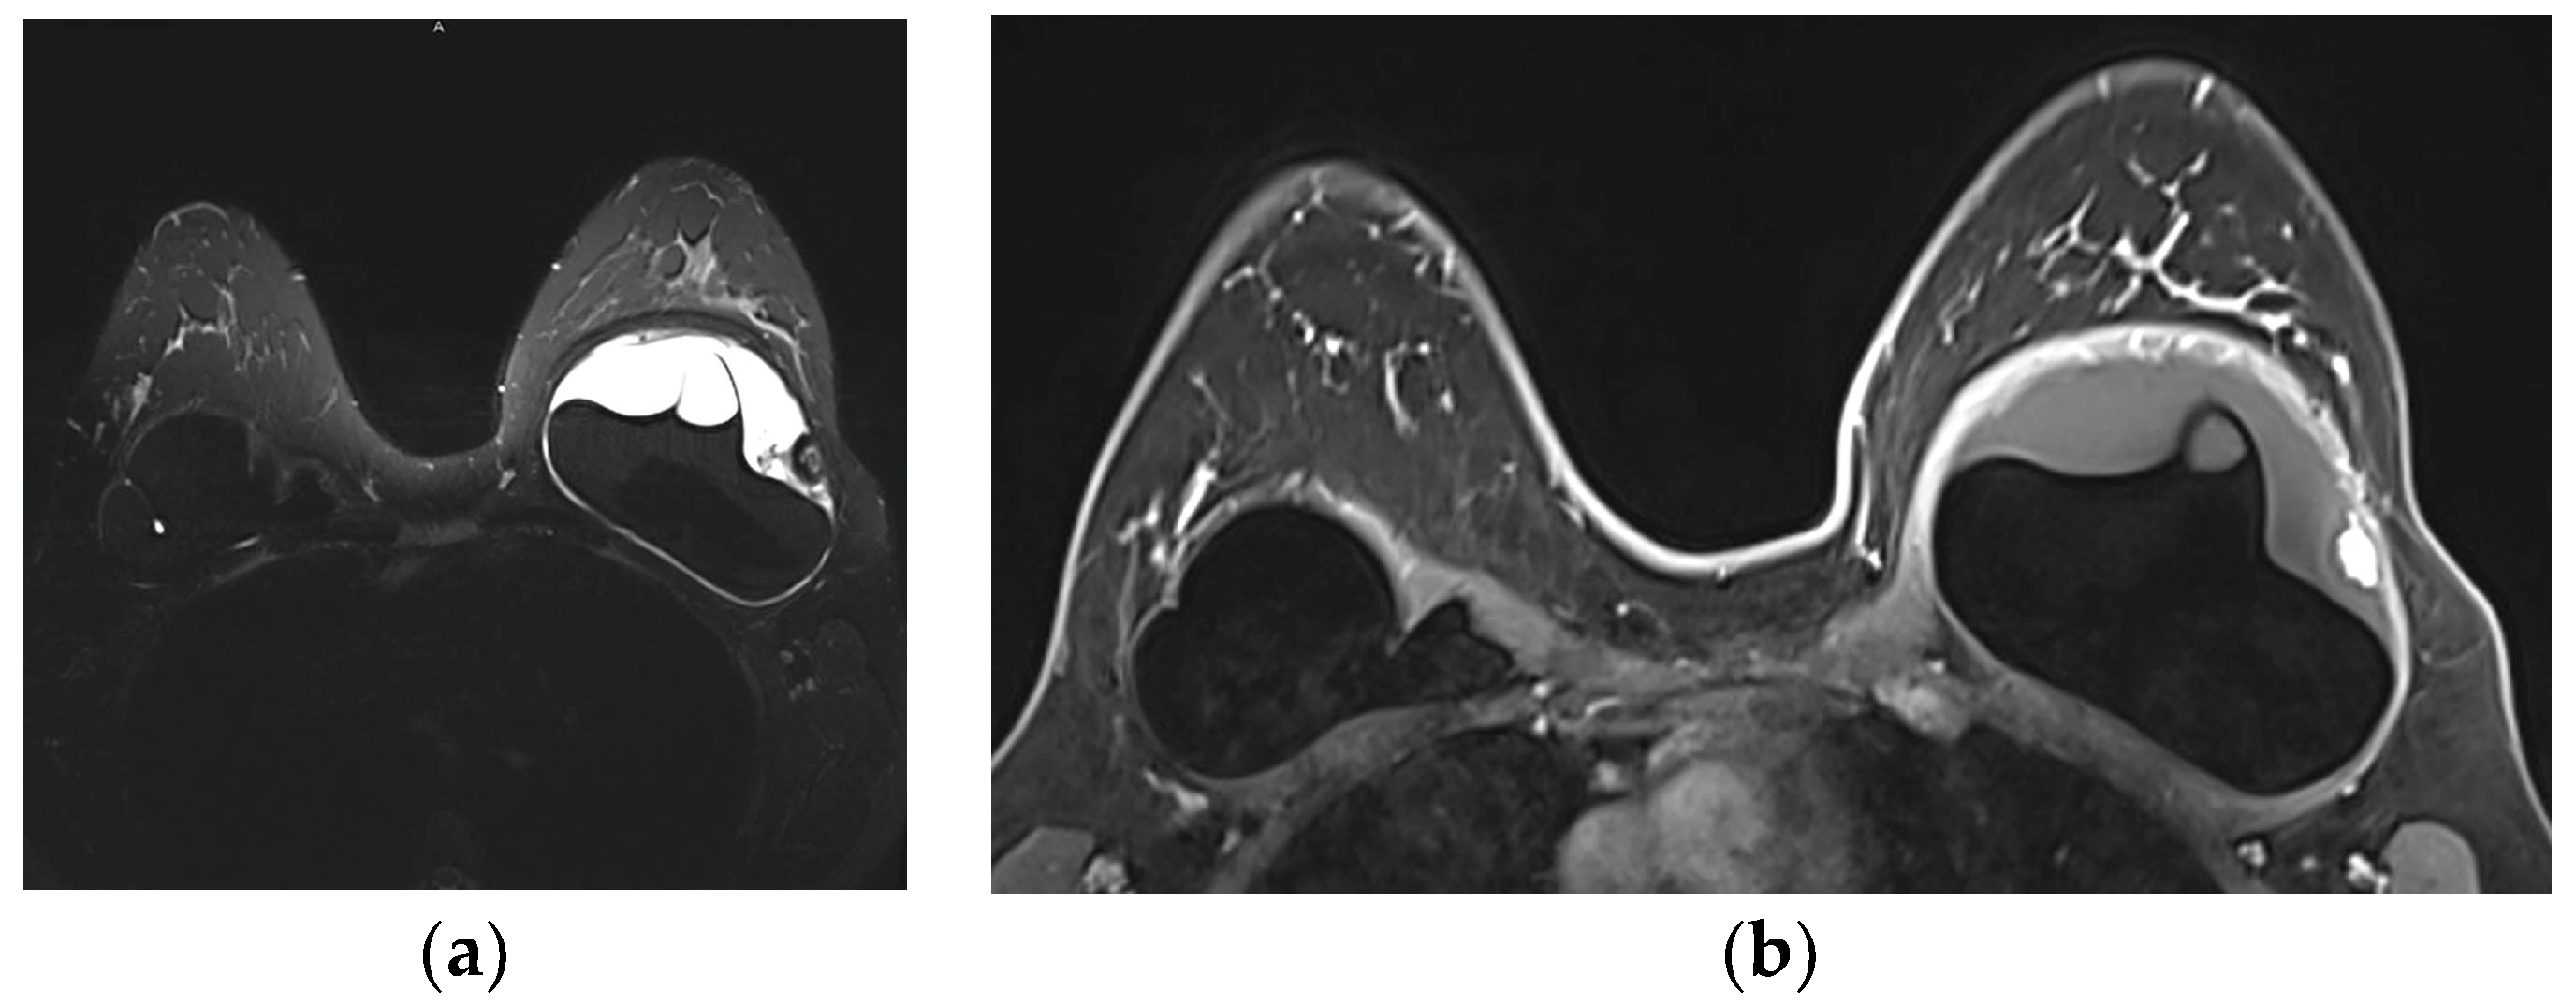

5.2.5. Implant Rupture

5.2.6. Breast Implant Associated Atypical Large Cell Lymphoma (BIA-ALCL)

- Sharma, B.; Jurgensen-Rauch, A.; Pace, E.; Attygalle, A.D.; Sharma, R.; Bommier, C.; Wotherspoon, A.C.; Sharma, S.; Iyengar, S.; El-Sharkawi, D. Breast Implant-associated Anaplastic Large Cell Lymphoma: Review and Multiparametric Imaging Paradigms. Radiographics 2020, 40, 609–628. [Google Scholar] [CrossRef] [PubMed]

- Adrada, B.E.; Miranda, R.N.; Rauch, G.M.; Arribas, E.; Kanagal-Shamanna, R.; Clemens, M.W.; Fanale, M.; Haideri, N.; Mustafa, E.; Larrinaga, J.; et al. Breast implant-associated anaplastic large cell lymphoma: Sensitivity, specificity, and findings of imaging studies in 44 patients. Breast Cancer Res. Treat. 2014, 147, 1–14. [Google Scholar] [CrossRef] [PubMed]

- Rotili, A.; Ferrari, F.; Nicosia, L.; Pesapane, F.; Tabanelli, V.; Fiori, S.; Vanazzi, A.; Meneghetti, L.; Abbate, F.; Latronico, A.; et al. MRI features of breast implant-associated anaplastic large cell lymphoma. Br. J. Radiol. 2021, 94, 20210093. [Google Scholar] [CrossRef]

| Signs | Details | |

|---|---|---|

| Definitive rupture | Linguini sign | Low signal lines within the silicone |

| Subcapsular lines | Low signal lines parallel to the capsule surrounded by silicone | |

| Free Silicone | Extracapsular silicone | |

| Possible rupture | Keyhole or teardrop Sign | Focal silicone invagination between implant shell and fibrous capsule |

| Salad-oil sign Rat-tail sign | Silicone gel mixed with peri-implant fluid Contour irregularity extending along the chest wall | |

| Pitfalls | Complex radial folds | Long invaginations of the shell |

| Gel bleed | Silicone within the axillary lymph nodes | |

| Double-lumen implant | Inner compartment shell may mimic intracapsular rupture |